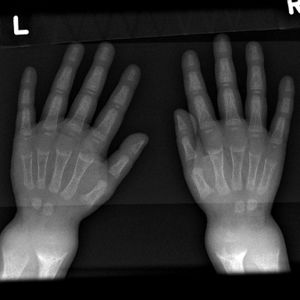

Wrist X ray showing changes in rickets, mainly cupping is seen here.

- توسع المعصم[4] raises early suspicion, it is due to metaphysial cartilage hyperplasia.

توسع المعصم

- شعاعياً: يكون التشخيص الباكر للرخد الفعال أفضل ما يكون في المعصم، لأن التبدلات المميزة في نهاية الزند والكعبرة تحدث في المراحل الباكرة. تتسمك المنطقة الغضروفية ويزداد عرض النهاية البعيدة لجسم العظم، فتبدو متسعة ومقعرة ومهترئة وتنقص كثافة جسم العظم.